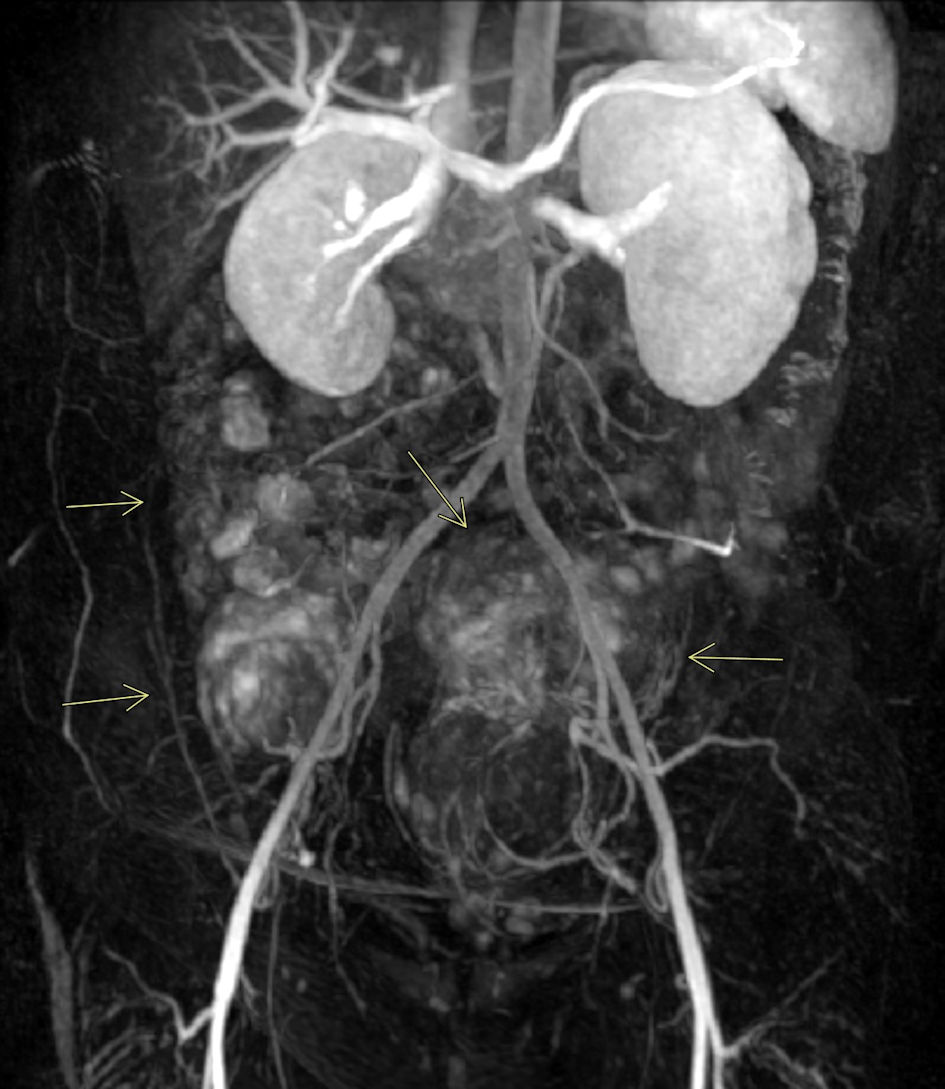

UFE was then performed using standard interventional radiology technique. Moderate sedation was given using Versed (Pfizer Inc. New York, NY) 1 mg intravenous (IV) and fentanyl (Janssen Pharmaceutical Athens, GA) 50 µg IV. A conventional aortic angiogram and a selective iliac artery angiogram were performed. The left uterine arteriogram demonstrated a prominent vascular blush consistent with large fibroids, correlating with prior MRI findings. A single, enlarged left uterine artery was noted supplying the markedly enlarged fibroid uterus. A TriSalus TriNav Infusion System (Trisalus Life Science Westminster, CO) antireflux infusion microcatheter was placed through the diagnostic catheter and advanced into the left uterine artery, and selective arteriogram was performed (Fig. 3). Intra-arterial embolization was performed with Terumo Hydropearl 200 - 400 µm microspheres.

Figure 3. Selective left iliac conventional angiogram. Left iliac artery angiogram demonstrates prominent hypervascular fibroids occupying a substantial portion of the left uterus (arrows).